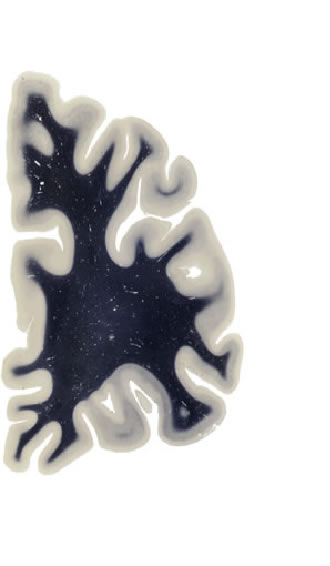

Hi-Resolution Sections · Cells (Nissl Staining) · Virtual Microscopy

Frontal sections (Nissl) from the Atlas Brain:

Slice ID:

r2-1027

Plate NR:

06

Position:

-30,6 mm